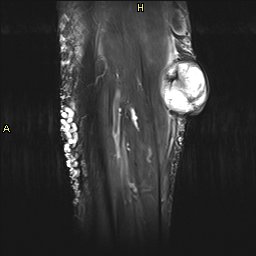

Lo que ves en estas imágenes que te voy a poner aquí son los hallazgos ecográficosque he podido visualizar hoy. Los voy a complementar con la correlación con las imágenes de TAC. En este caso específico con la eco solo se pudo corroborar los hallazgos del escáner, que a nivel anatómico arroja un mejor desarrollo de la anatomía regional implicada en el proceso.

6En el corte longitudinal de la imagen 1 ya se ve una vaso perimetrado por una imagen hiperecogénica, no compresible a la presión con la sonda convexa. En la imagen 2 con la sonda lineal se observa el enrejado habitual de los stents, que en otras ocasiones ya hemos comentado en otro post en localización distinta.

Finalmente, imagen 5 y 6 que te enseñan el tratamiento aplicado a las gonadales de forma bilateral, embolizadas con material hiperecogénico en su interior que en la reconstrucción coronal del CT se objetiva como una imagen bilateral brillante lateral a los grandes vasos.